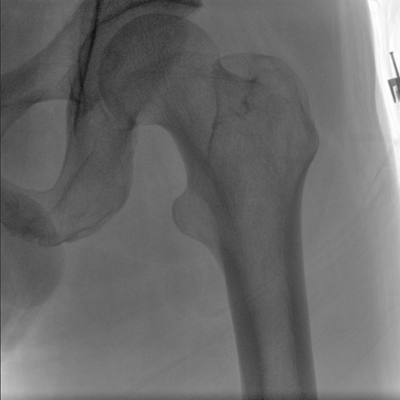

大尺寸動態平板探測器,高DQE、低噪聲、圖像清晰。采用多分辨率圖像增強處理技術,不同部位不同圖像處理算法,滿足客戶多樣化的需求。

采用智能變頻脈沖透視技術,優化圖像質量的同時降低輻射劑量,呵護醫患健康

多角度自由旋轉,滿足患者復雜擺位需求。